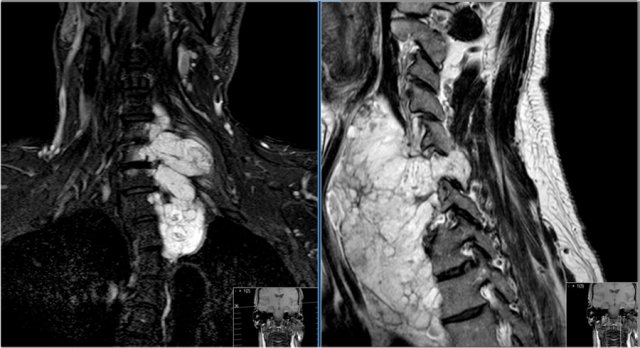

Chordoma (2)

Here another case of the cervical spine.

T2 weighted images with and without fat suppression.

Notice the involvement of more than one vertebral level, extensive soft tissue mass and very high signal intensity.